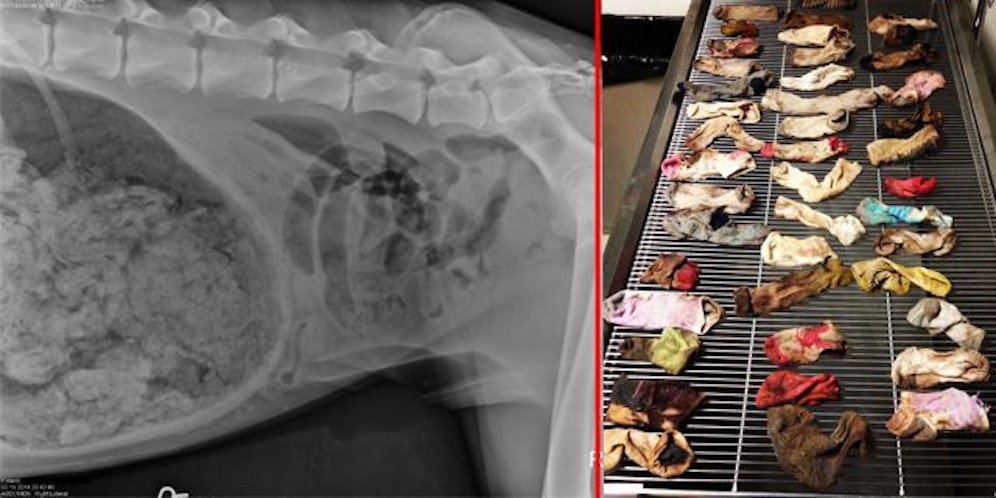

Die Ärzte des DoveLewis Emergency Animal Hospital in Pettygrove in Portland schnappten sich die Dogge und schickten sie erstmal zum Röntgen. Die Aufnahmen zeigten laut Krankenakte "eine große Menge an Fremdkörpern".

Ore wurde sofort in den OP geschoben, wo Ashley Magee die Dogge zwei Stunden lang operierte. Sie traute ihren Augen kaum. In mühevoller Kleinstarbeit holte sie 43 Socken und eine halbe aus dem Verdauungstrakt des Hundes.